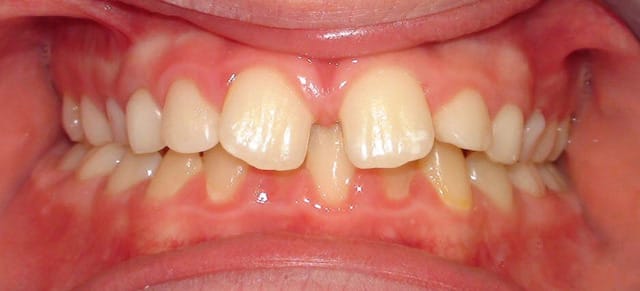

À votre avis, au vu de la téléradio de profil, 13 et 23 sont-elles incluses en vestibulaire ou en palatin ?

Je vous joins également pour faire plaisir à certains des photos intra-buccales bien qu'elles n'apportent absolument rien de plus.

si, si, si, classe d'angle, ddm, supraclusion, volume des arcades, etc...

OK, on voit une supraclusie incisives, mais pas de DDM et j'en aurais parlé dès le départ si ça avait pu apporter quelque chose au plan de traitement.

Et on voit aussi la vestibuloversion de la 22 qui est effectivement un signe positif d'inclusion vestibulaire de la canine. Dans ce sens, tu as raison.